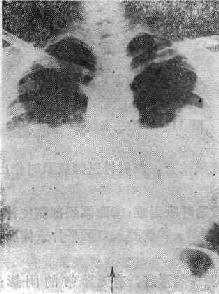

(一)中央型肺水肿 以两肺门为中心向两肺野扩展的阴影(可见支气管气影征),由深变淡,肺野边缘、肺尖和肺底清晰,呈“蝶翼状”分布,这是中央型肺水肿典型的X线表现(图114-1)。常见于心脏和尿毒症患者。治疗及时一般很快吸收消失(3天之内);如治疗不及时,肺泡内除渗液外,可以为凝固的纤维蛋白和巨噬细胞所充填。可产生炎性改变。肺水肿可继发感染。

图114-1 心源性肺水肿的X线表现